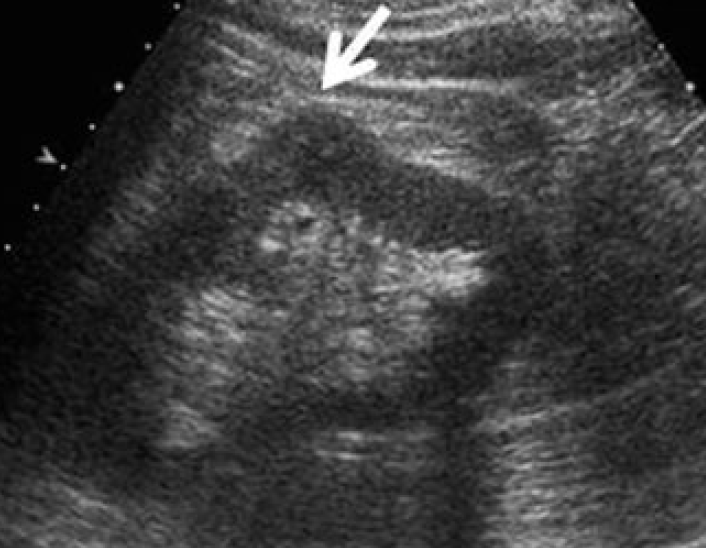

1-Hypertrophied column of Bertin

أعتقد بأن هذا من أهم المتغيرات التي قد يشتبه في كونها ورم. هي ببساطة تضخم لنسيج الكلية parenchyma إلى الداخل sinuses مرورا بين الأهرامات الكلوية medullary pyramids.

يميزه تناسق echogenicity بينه وبين باقي parenchyma بالإضافة لعدم وجود ارتفاع أو تغير ملحوظ في قراءات colour Doppler. غالبا لا يزيد عرضه عن ٣ سم.